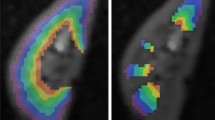

Example intravoxel incoherent motion (IVIM) and diffusion tensor imaging (DTI) maps from a healthy volunteer left kidney. Left: biexponential IVIM fitting of multiple b-value data provides maps of perfusion fraction (fp), tissue diffusion (Dt), and pseudo diffusity (Dp). Right: DTI tensor fitting of multidirectional data provides maps of mean diffusivity (MD), fractional anisotropy (FA), directivity, and principal diffusion orientation (v1)

IVIM and DTI parameters estimated on the original data without processing (no correction—bottom rows) and after distortion and motion compensation (top rows) for a representative subject. The columns correspond to the slow diffusion (D), fast diffusion (D*), perfusion fraction (f) of the IVIM model and the mean diffusivity (MD), and fractional anisotropy (FA) parameters of the DTI model. The parameter maps obtained after distortion and motion compensation processing have fewer outliers and discontinuities. Moreover, the medulla and cortex can be better identified in the perfusion fraction (f) and fractional anisotropy (FA) maps of corrected images